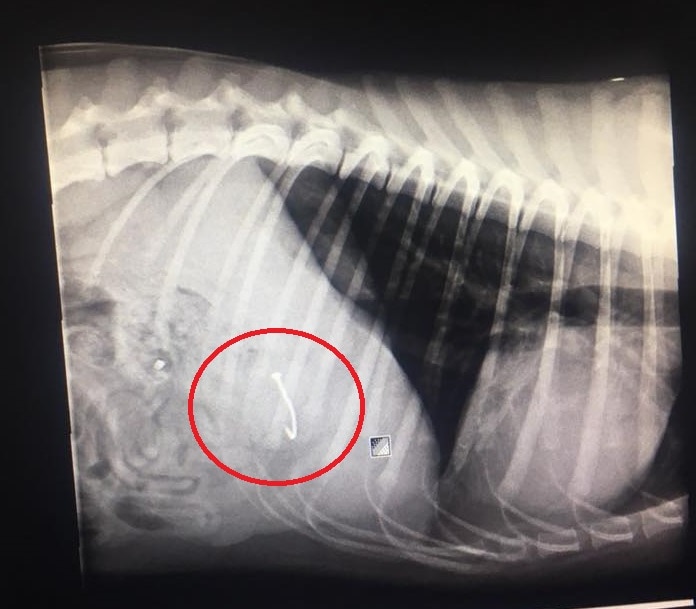

Dog Swallows Discarded Fishing Hook On Beach Emergency Surgery Costs Owner 2 700 Abc News